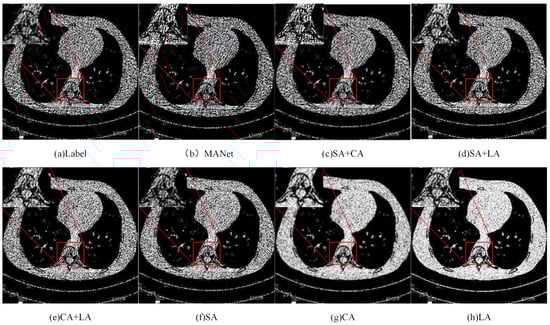

Figure 9 shows the prediction results of the network with different attention mechanism combinations on the test image. Each column in the figure corresponds to a network model or attention mechanism combination. The red rectangle and the enlarged details show the detection effect of each model on lung nodules. The MANet model proposed in this paper performs best in noise control and detail restoration, and is closest to the true label. The network with different attention mechanisms also has significant improvements in detection effect, but each has its own emphasis. SA+CA and CA+LA combinations perform relatively balanced in detail restoration and noise control. SA+LA combination performs well in details, but noise control is slightly worse. The attention mechanisms (SA, CA, LA) used alone are not as effective in detail restoration and noise control as the combination, but each has its own advantages.

Figure 9.

Predicted results of networks with various attention mechanism combinations on test images.

To evaluate the independent contribution of each attention module, we removed each module separately and recorded the change in model performance. We compared the performance of the complete model, which includes all attention modules, with the performance of the model after removing a single attention module. In these experiments, we tested different combinations of the three types of attention modules. By comparing the performance of these combinations, we can more clearly understand the contribution of each module to the model’s denoising performance. Six additional networks were designed, each representing a different combination of attention modules. The specific combinations are as follows: SA (Spatial Attention only), CA (Channel Attention only), LA (Scale Attention only), SACA (Spatial + Channel Attention), SALA (Spatial + Scale Attention), CALA (Channel + Scale Attention), MANet (all attention).

As seen in Figure 8, the MANet model, which includes all three attention modules (spatial, channel, and scale attention), demonstrates the best performance in terms of both training loss and L1 loss on the test set. The SA, CA, and LA models, each utilizing only one type of attention module, showed some improvement in denoising performance. However, their performance did not match that of networks combining two or three attention modules. Among them, the SA module performed the best, indicating that spatial attention has a significant advantage in handling multi-scale noise. The SACA, SALA, and CALA combinations outperformed the single attention modules, demonstrating that the synergy of multiple attention mechanisms can effectively enhance denoising performance. The SACA combination performed nearly the best among all combinations, validating the advantage of combining spatial and channel attention for LDCT image denoising. The full MANet model, integrating spatial, channel, and scale attention modules, achieved the lowest training loss and test loss values. This indicates that a comprehensive consideration of multiple attention mechanisms can more thoroughly address and suppress noise in LDCT images.